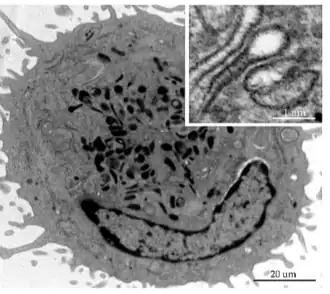

Célula de Langerhans aislada. Gránulos de Birbeck en recuadro, arriba derecha. Microscopía electrónica.

El núcleo es dentado con circunvoluciones o bien lobulado.

El citoplasma es electrolúcido, desprovisto de tonofilamentos y melanosomas.[9]

Inicialmente se identificaron por un marcador citoplasmático específico, el gránulo de Birbeck, un orgánulo denso en electrones.

La célula CL muestra ausencia de desmosomas.[9]